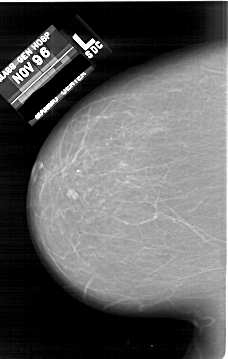

A_1623_1.RIGHT_MLO

RIGHT_MLO LINES 6496 PIXELS_PER_LINE 4501 BITS_PER_PIXEL 12 RESOLUTION 43.5 OVERLAY